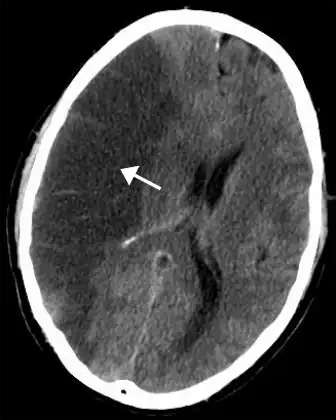

An aneurysm is an abnormal bulging of small sections of arteries, which increases the risk of artery rupture. Intracranial aneurysms are a leading cause of subarachnoid hemorrhage, or bleeding around the brain within the subarachnoid space. There are various hereditary disorders associated with intracranial aneurysms, such as Ehlers-Danlos syndrome, autosomal dominant polycystic kidney disease, and familial hyperaldosteronism type I.[26][27][28] However, individuals without these disorders may also obtain aneurysms. The American Heart Association and American Stroke Association recommend controlling modifiable risk factors including smoking and hypertension.[29]